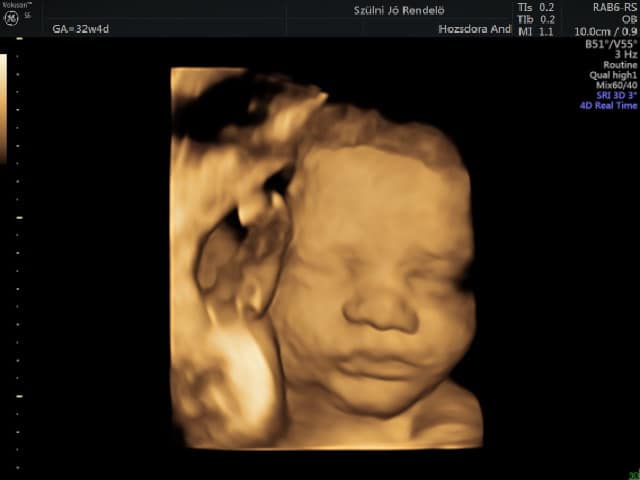

4D kép: valós idejű 3D mozgókép. A magzatvíz olyan körülményeket teremt, hogy a magzat nagyon plasztikusan ábrázolható, emiatt használjuk az ultrahang vizsgálat során. A kép minősége attól függ, hogy van-e elég folyadéktér a magzat arca előtt. Ha a magzat arca túl közel van a méhfalhoz, vagy a placenta felszínéhez, akkor nincs lehetőségünk szép képet készíteni. Ilyenkor meg kell várnunk a megfelelő helyzetet. Így a 3-4D sikere is nagyrészt a magzati pozíciótól függ, illetve befolyásolja az anyai szövetek tulajdonsága is, mint ahogy a 2D ultrahang minőségét is.